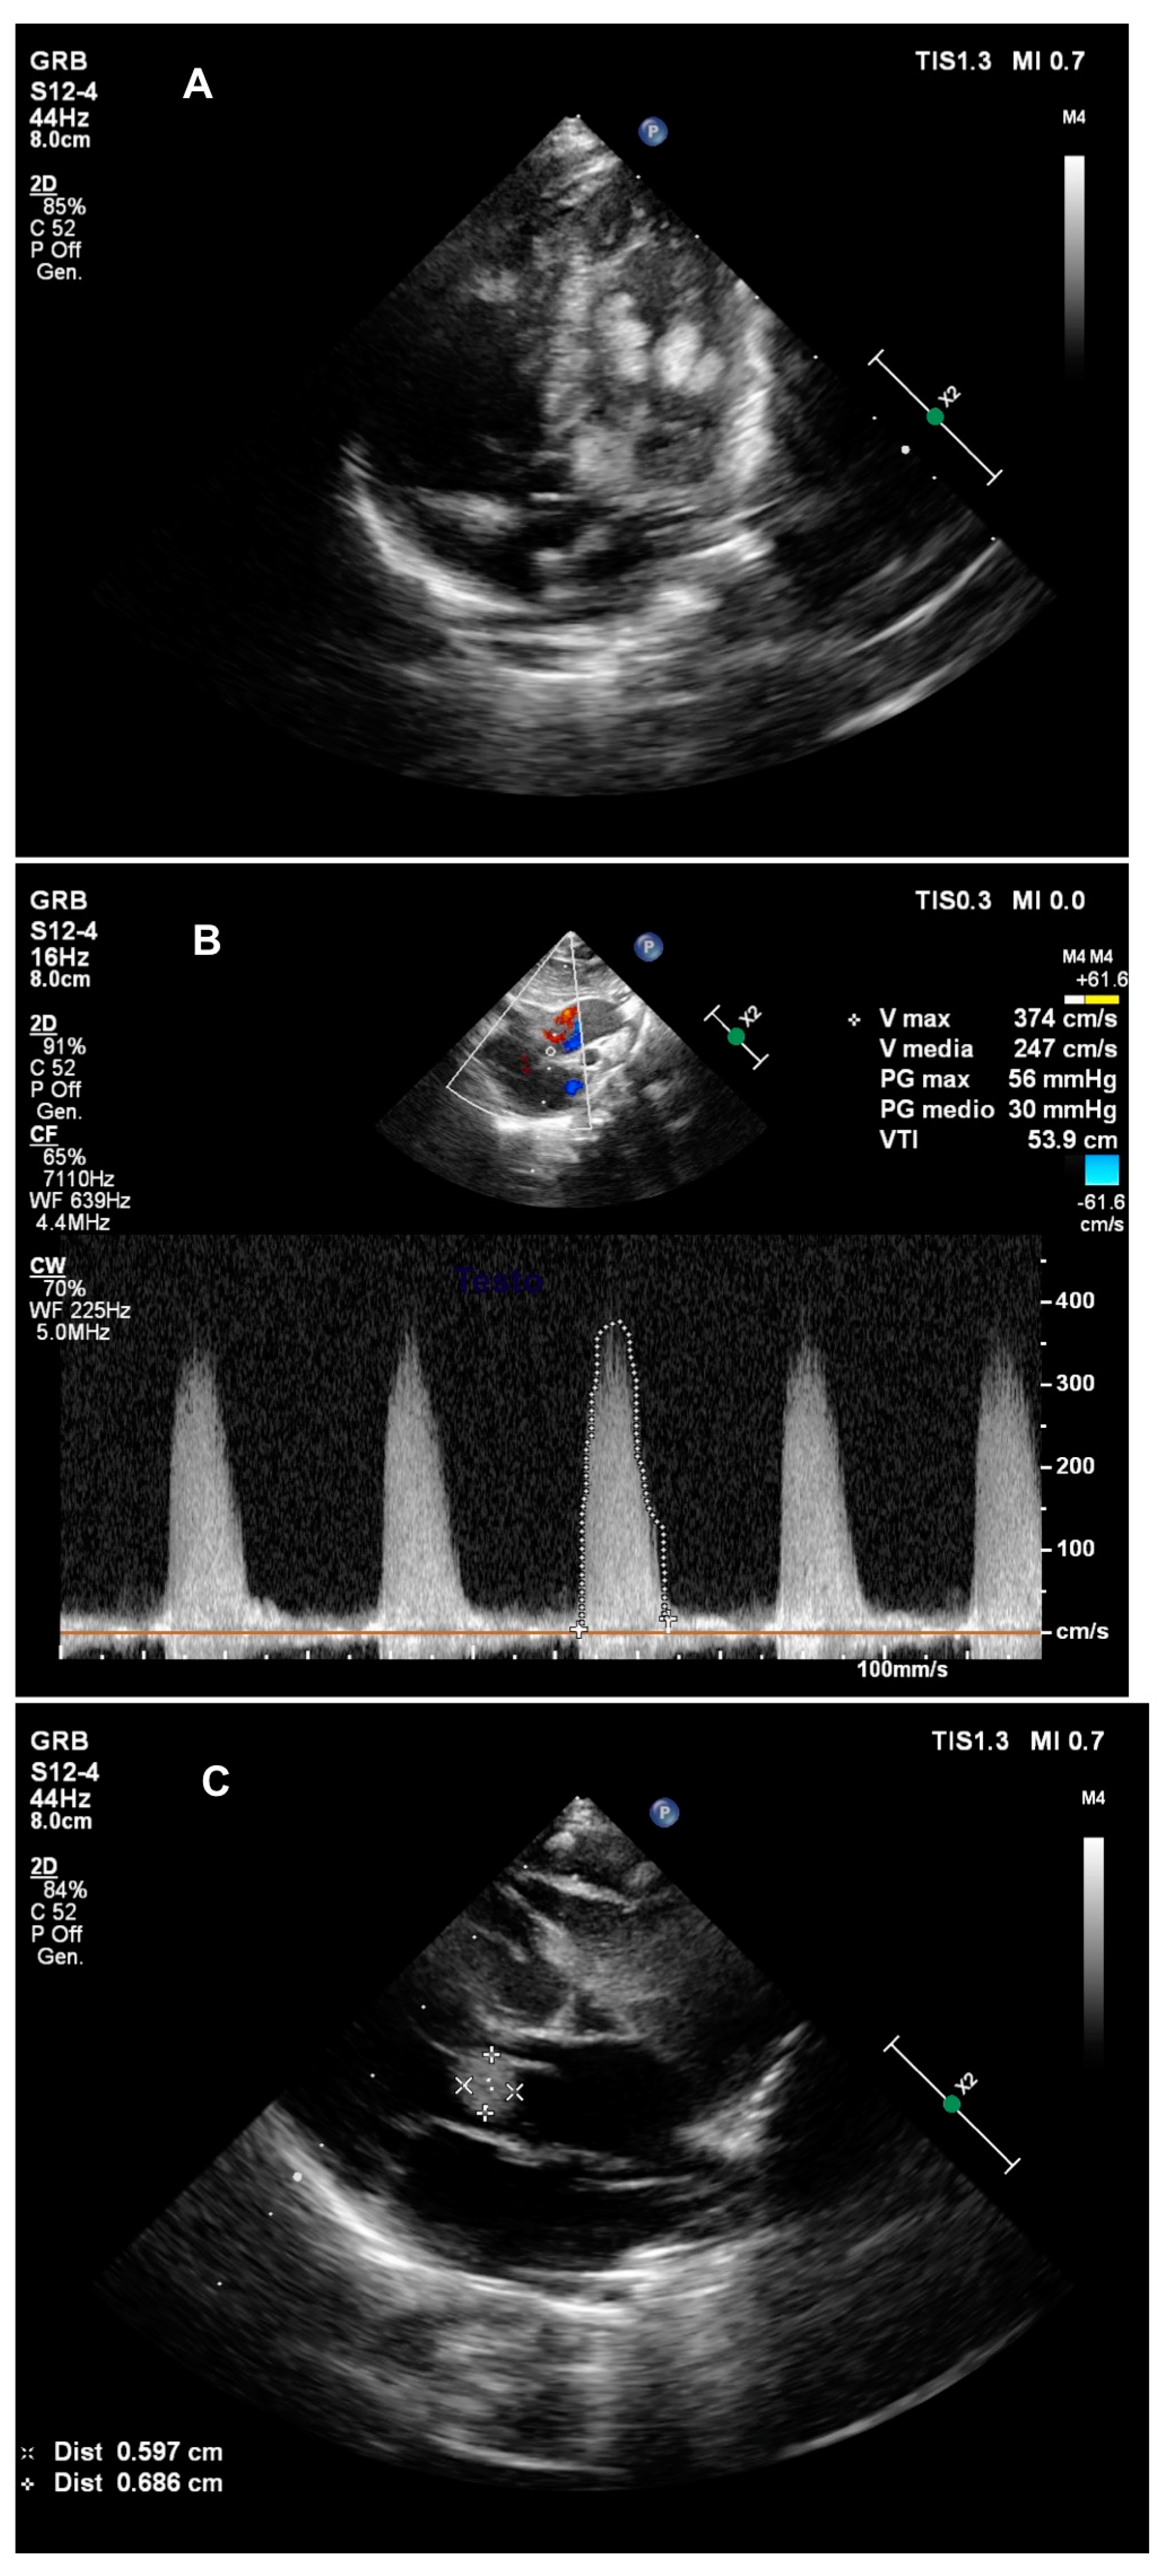

2. Case Presentation